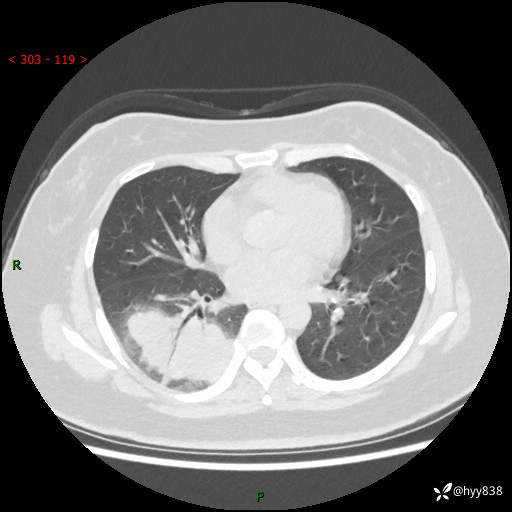

大叶性肺炎的表现形式,晒晒鉴别诊断吧…结果公布~

简要病史:患者8天前无明显诱因出现咳嗽、咳痰,为绿色脓痰,无明显加重与缓解因素,无高热、寒战,无呼吸困难,无大量脓痰,无哮鸣音,于当地医院行胸片示右下肺团块影,性质待定,予口服药物治疗症状未见明显改善,具体药名不详,为求进一步诊治来我院就诊,门诊以“肺占位性病变”收入我科进一步诊治。 患者自发病以来,精神、饮食尚可,睡眠欠佳,大小便正常,体力、体重未见明显异常。

辅助检查:CT

胸部CT平扫